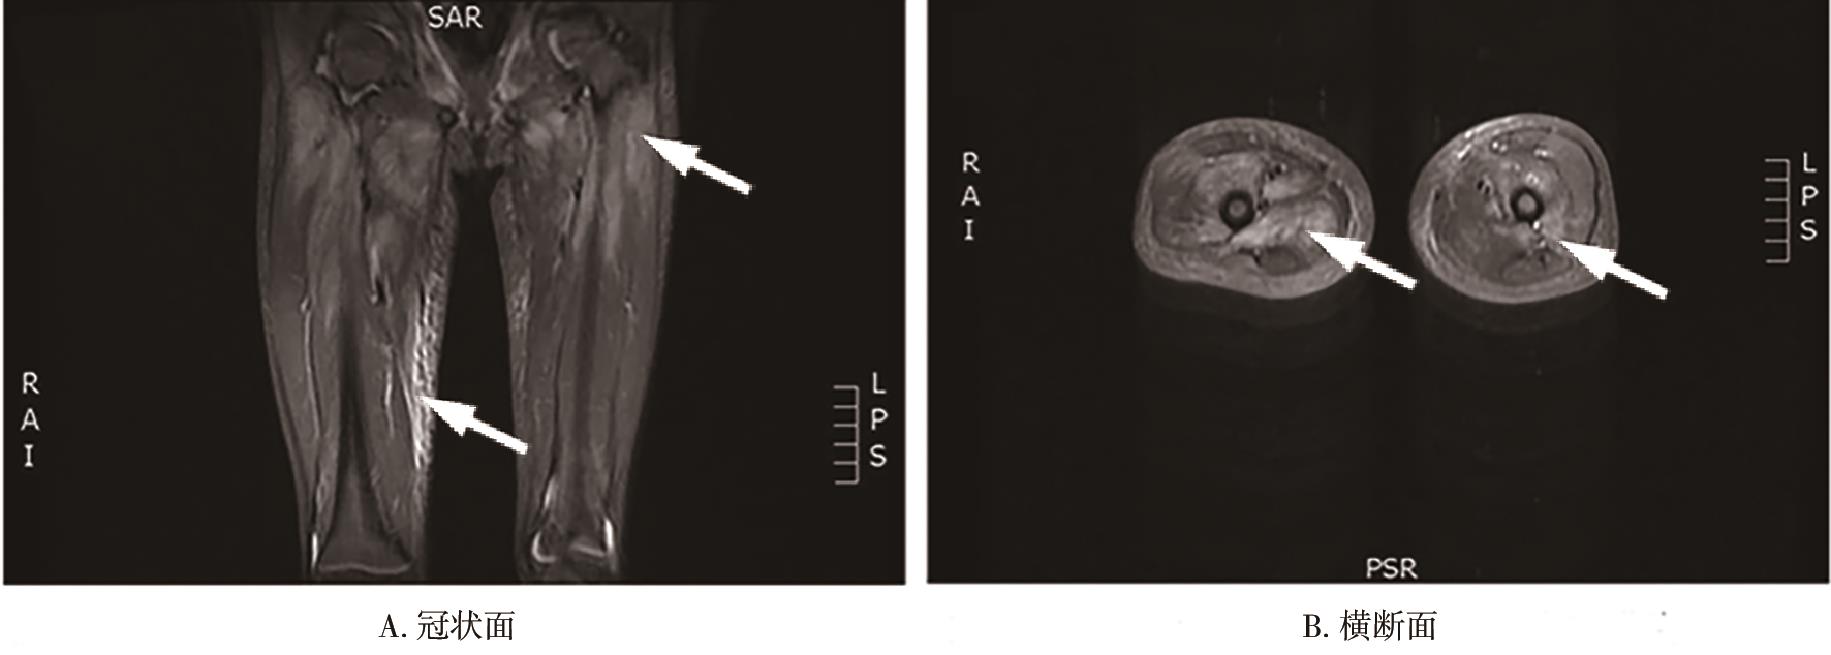

• 儿童横纹肌溶解症合并心包填塞、心肌肥厚1例报道

2023, 48(3):362-365. DOI: 10.13406/j.cnki.cyxb.003034

摘要 (107) HTML (36) PDF 9.91 M (361) 评论 (0) 收藏